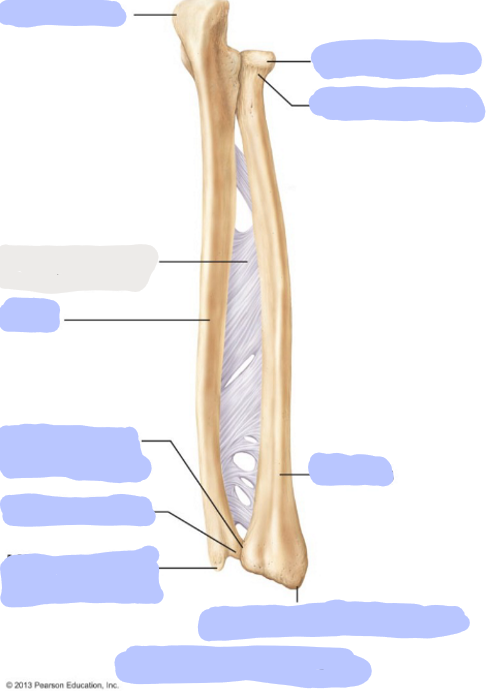

What is this picture of?

Posterior view of the forearm including the Ulna and Radius

What is here?

Where is the Ulna of the forearm?

What is here?

Where is the Radius of the forearm?

What is here?

Where is the Olecranon of the Ulna?

What is here?

Where is the Head of the Ulna?

What is here?

Where is the Ulnar styloid process?

What is here?

Where is the Head of the Radius?

What is here?

Where is the Neck of the Radius?

What is here?

Where is the Radial Styloid Process of the Radius?

What is here?

Where is the Ulnar notch of the radius?